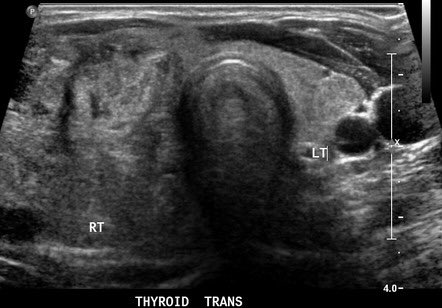

رابعاً : فحص الغدة الدرقية عن طريق الاشعة الصوتية .

يتم تقسيم نتيجة الفحص على اساس الاشعة الصوتية الى ٥ مستويات - تقسيم TI-RAD

الدرجة الاولى و الثانية لا تحتاج الى اخذ عينة و يمكن متابعتها عن طريق العيادات و اعادة فحص الاشعة الصوتية .

اذا كانت الدرجة اكثر من ٢ عندها يجب عمل عينة للغدة الدرقية و التي تتم عن طريق ابرة صغيرة تحت التخدير الموضعي بمساعدة الاشعة الصوتية ، يقوم بها طبيب الاشعة التداخلية .